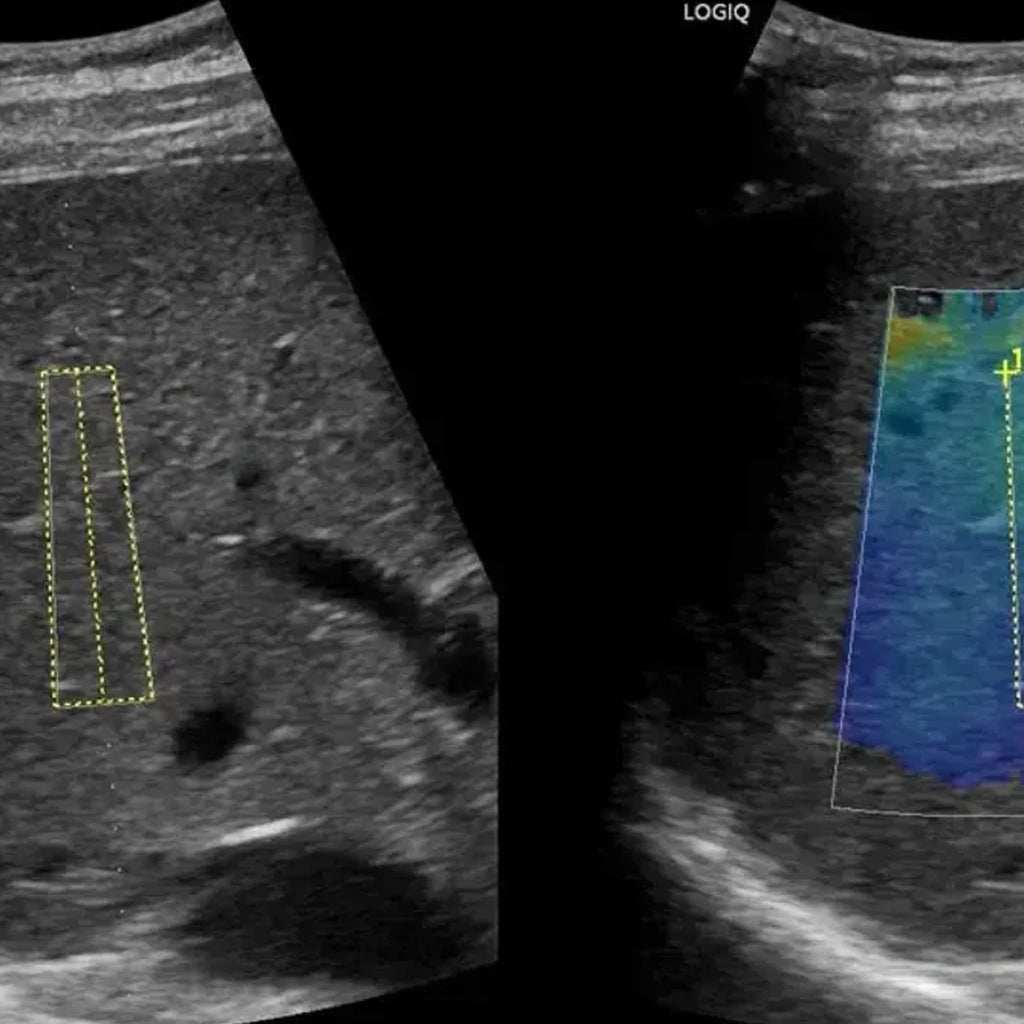

El ultrasonido de pared abdominal para hernia inguinal es un estudio de imagen no invasivo que utiliza ondas sonoras para evaluar la presencia y características de una hernia inguinal (protusión de tejidos o órganos abdominales a través de una debilidad o defecto en la pared abdominal inferior).